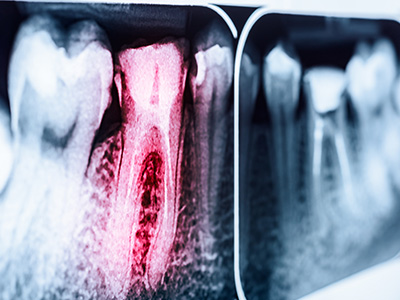

We are in a beautiful area, surrounded by mountains with their trees and plants. What we don’t see are the roots of those plants that sustain what is above the ground. Similarly, a tooth must have a root to survive and function. We have the skills, knowledge, and dedication to save teeth when others can’t. We preserve the roots to save teeth, protecting your time and health.

While many may resort to extractions and implants, at Mountain Health Dentistry, we stand confident in preserving natural dentitions. Our expertise lies in performing high-quality, patient-centered, laser-assisted, non-surgical root canal treatments, retreatments, and root-end microsurgeries.

Too often a tooth is extracted that could have been saved from a misdiagnosed vertical root fracture or an “it’s infected” extraction. Maintaining one’s teeth contributes to a better quality of life, better health, and longer life expectancy. We preserve the root to save the tooth, protecting your time and health.